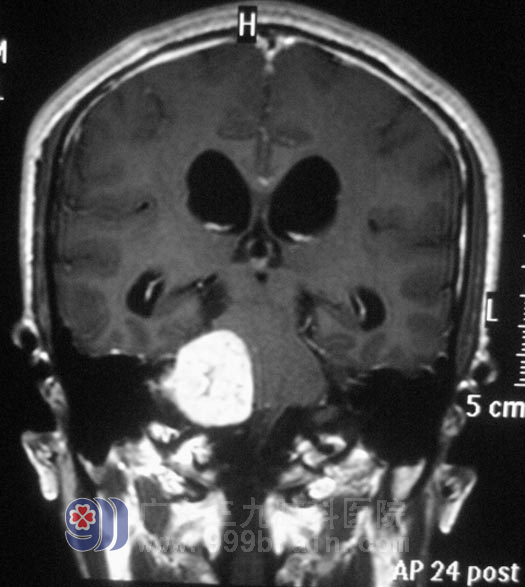

区先生,今年44岁。五年前开始出现右耳听力下降,间断头晕,呈阵发性,当地医院考虑是五官科问题,予对症治疗后症状无明显好转,且右耳听力下降不断加重。三个月前,他逐渐出现双眼视力下降,间断头晕伴有恶心感。头颅CT检查,结果提示“右侧桥小脑角区占位,约3.5cm×3.2cm,考虑听神经瘤,伴梗阻性脑积水”。

入住广东三九脑科医院综合神经外科时,区先生左侧侧鼻唇沟变浅,露齿时口角向右侧歪斜,双耳听力下降(右耳明显),闭目难立征(+),易向右侧倾倒。12月20日,由鲁明主任主刀,在全麻下行右侧乙状窦入路听神经瘤切除术。术中显微镜下见黄白色肿瘤组织,位于右侧桥小脑角区,质软,血供丰富,面神经位于肿瘤前下方,副神经、迷走神经、舌咽神经位于肿瘤后下方,神经组织形态菲薄,在显微镜下用超声刀分块切除,磨钻磨除部分内听道,切除内听道内肿瘤组织,中后组颅神经保护完好,手术顺利结束。术后病理结果为:(右侧桥小脑角)神经鞘瘤。